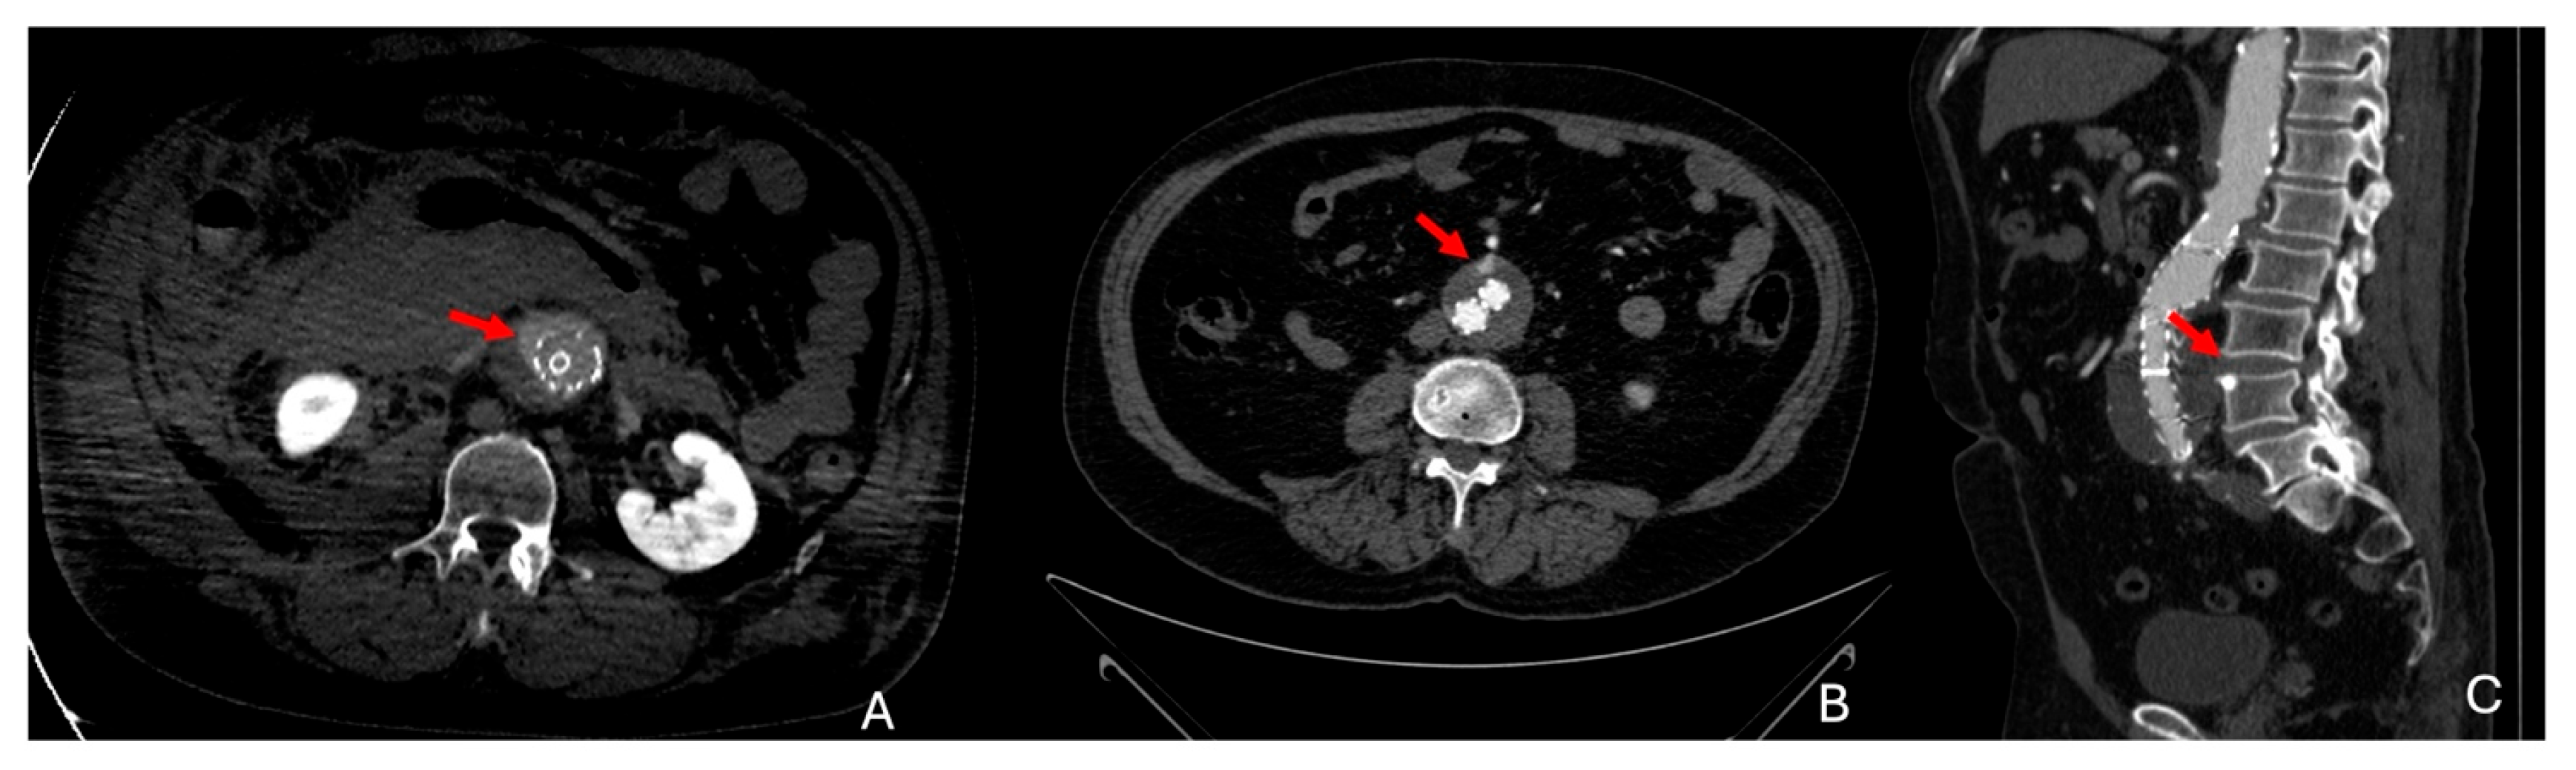

8.1. Infected Aneurysm

- Macedo, T.A.; Stanson, A.W.; Oderich, G.S.; Johnson, C.M.; Panneton, J.M.; Tie, M.L. Infected Aortic Aneurysms: Imaging Findings. Radiology 2004, 231, 250–257. [Google Scholar] [CrossRef]

- Lee, W.-K.; Mossop, P.J.; Little, A.F.; Fitt, G.J.; Vrazas, J.I.; Hoang, J.K.; Hennessy, O.F. Infected (Mycotic) Aneurysms: Spectrum of Imaging Appearances and Management. RadioGraphics 2008, 28, 1853–1868. [Google Scholar] [CrossRef] [PubMed]

| Infected | In the context of systemic infection, more common in immunocompromised patients | Secondary to bacterial infection | - Fever - Abdominal pain - Elevated inflammatory markers - Risk of rapid expansion and rupture | Saccular aneurysm with periaortic gas, inflammatory signs 18FDG PET: Increased uptake in infected areas |